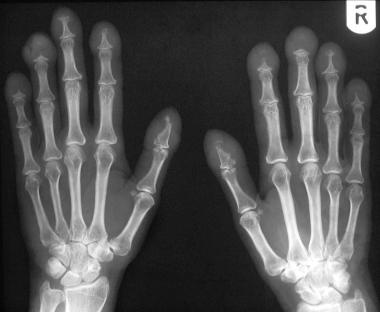

Lung adenocarcinoma is associated with the following paraneoplastic syndromes:

Hypertrophic osteoarthropathy (a specific form of clubbing)